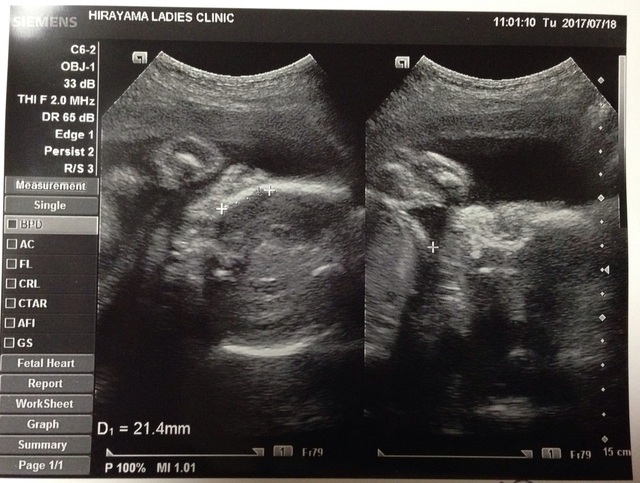

26週1日(26w1d・男の子)|KKK5413 さん(30歳)

エコー写真撮影時のエピソード:

全身が大きくなって映らなくなって残念だと思っていたのですが、この日初めて顔が見えてうれしかったです。画面では口をもぐもぐさせていて、動きがかわいかったです。

左側のエコー写真は頭部を上から写したところらしく、先生が耳の大きさは2cmと教えてくれました。どんどん大きくなってる!